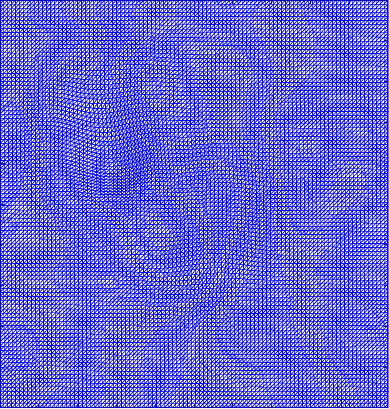

Figure 4 shows the visualisation of Figure 3 mappings in the form of grids. Let and be the Beltrami coefficients of the registration maps from the reference frame to the ground truth frame in Figure 3(a) and the perturbed frame in Figure 3(b) respectively. Figure 4(a) shows the mapping associated to Beltrami coefficient , and Fig 4(b) shows the mapping associated to BC . From Figure 4(c) and Fig 4(d), we can see that our method successfully restored the normal and abnormal deformation. Figure 4 serves as evidence that our decomposition is meaningful, in the sense that our method does not blindly return a Beltrami Descriptor with certain periodicity, but the decomposed descriptor does carry our desired information to recover the deformation to a large extent.